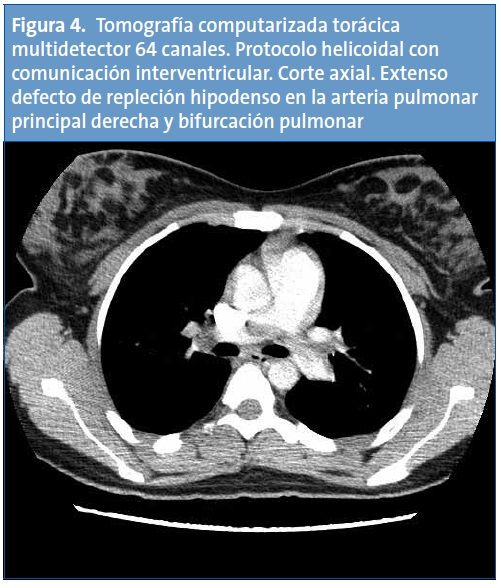

Con el diagnóstico de trombosis de vena cava inferior, se completa el estudio de imagen con una tomografía computarizada (TC) helicoidal de tórax, cuyos hallazgos son compatibles con defectos de repleción en las arterias pulmonares lobares de ambos lóbulos inferiores y en ambas arterias pulmonares principales, sin signos de dilatación del tronco de la arteria pulmonar ni evidencia de dilatación del ventrículo derecho. Los hallazgos radiológicos resultan compatibles con un tromboembolismo pulmonar (TEP) masivo (Figs. 3 y 4). En la TC abdominal se aprecia la extensión caudal del trombo a la vena cava inferior (Fig. 5).